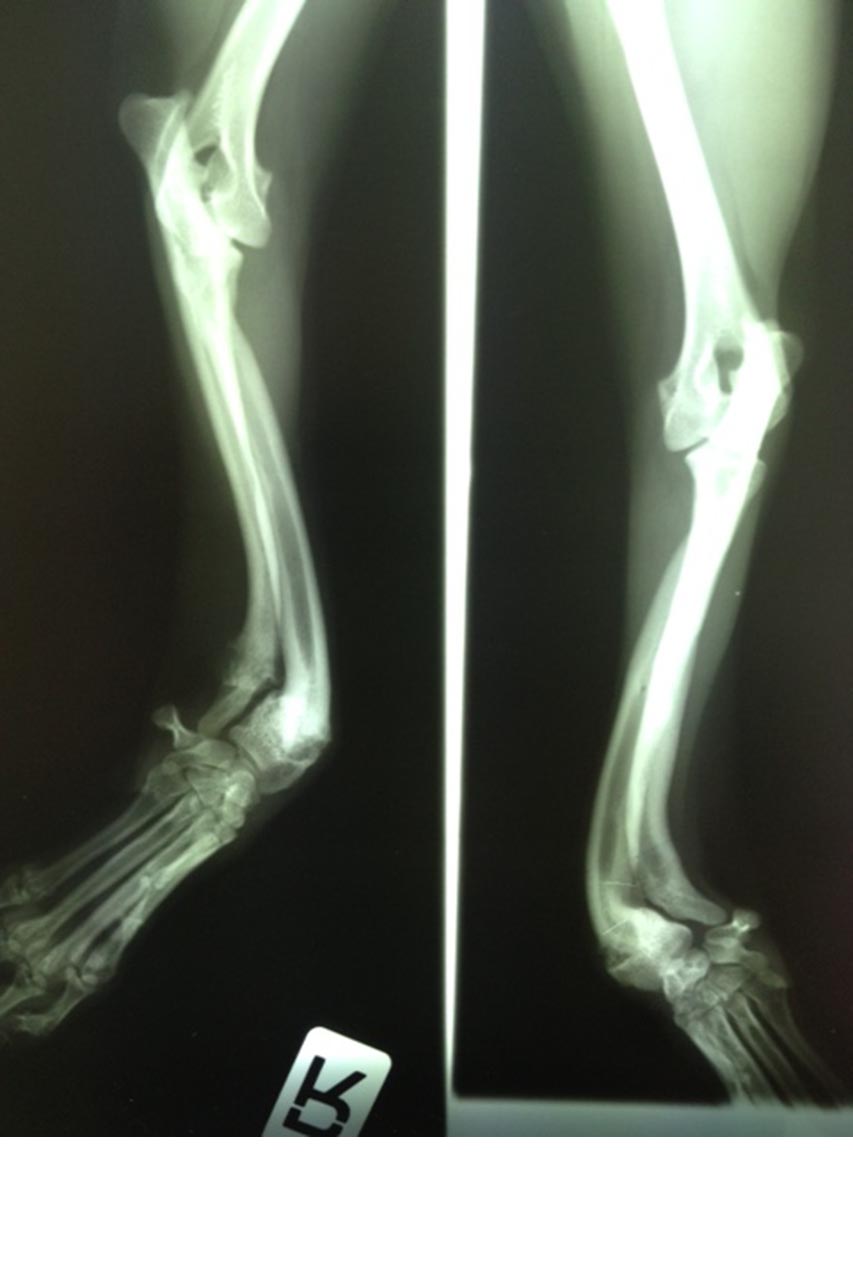

Viele aufwendige Operationen bei Knochenproblemen ließen wir durchführen. Wir haben uns immer von der Notwendigkeit und nicht von den Kosten leiten lassen. Felipa mit ihren verwachsenen Pfötchen ist sicher noch vielen in Erinnerung. Als die Rechnungen sich bei ihr auf über 5.000 Euro summierten, haben wir aufgehört mitzurechnen. Zum Glück sind das Ausnahmen. Dennoch waren es im Laufe der letzten 10 Jahre viele schwere Fälle, denen wir mit teuren Behandlungen wieder ein schönes Leben ohne Leiden verschafft haben.